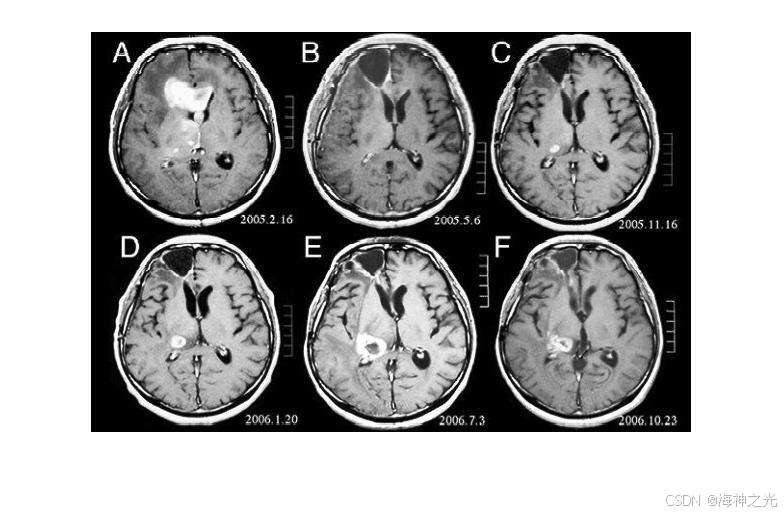

⛄三、运行结果